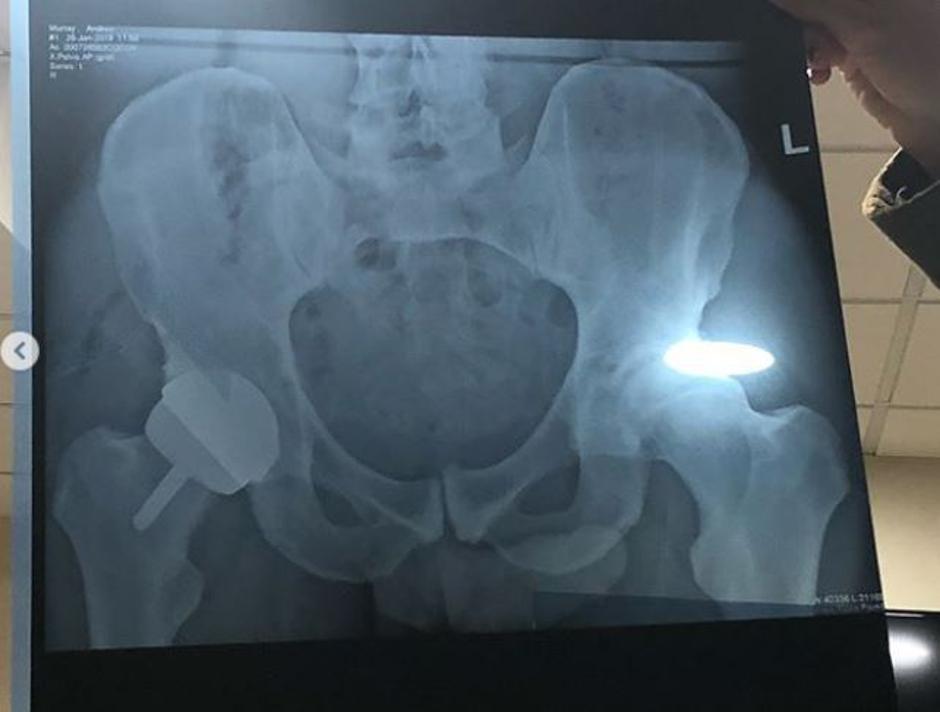

Teniški zvezdnik Andy Murray je na Instagramu objavil rentgensko fotografijo, ki je postala pravi viralni hit. "Kot lahko vidite na fotografijah, imam sedaj metalni kolk. Počutim se utrujeno in izčrpano, a pričakujem, da mi bo sedaj veliko bolje in da me ne bo več bolelo," je zapisal Murray.

Ob tem pa njegovi oboževalci niso izpustili te "podrobnosti", da je tenisač z rentgensko fotografijo svojih kolkov razkril tudi tisti najbolj intimni del svojega telesa. "Sem sem zašla le zaradi fotografije tvojega penisa. Sem razočarana? Niti malo," je zapisala ena izmed oboževalk. Murray te "podrobnosti" med objavo verjetno ni opazil, a fotografije tudi po številnih žgečkljivih komentarjih ni umaknil s svojega profila.